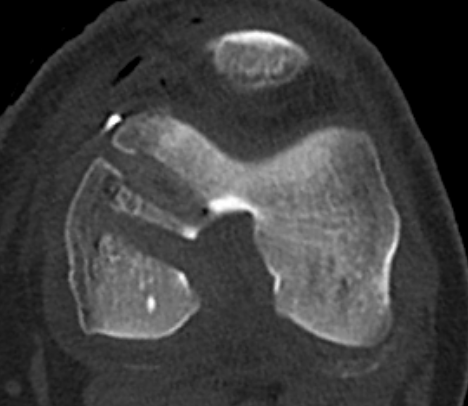

Acute femoral peel off of PCL

Acute Surgical Options

1. Repair bony avulsion

2. Acute suture repair of femoral peel off +/- augmentation

Acute repair of femoral peel off with suture tape augmentation

Indication

Femoral avulsion of the PCL

Acute injury

Technique

Repair to PCL to femoral insertion with sutures

Pass suture tape through tibial insertion to femoral insertion PCL to augment